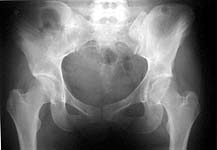

An example of closed ex-fix applcation in a similar case (pelcvic injury with posterior lesion) is attached. I put only AP views to decrease size of the posting.

if these xrays are all from the same case this is a very nice reduction. I would like to see the three views of the pelvis pre and post as well as the ct. kellam study showed 27% of unstable pelvis fractures maintained their reduction with an external fixation. Additionally, this case is through the si joint instead of the crescent fracture that was presented. These behave differently.